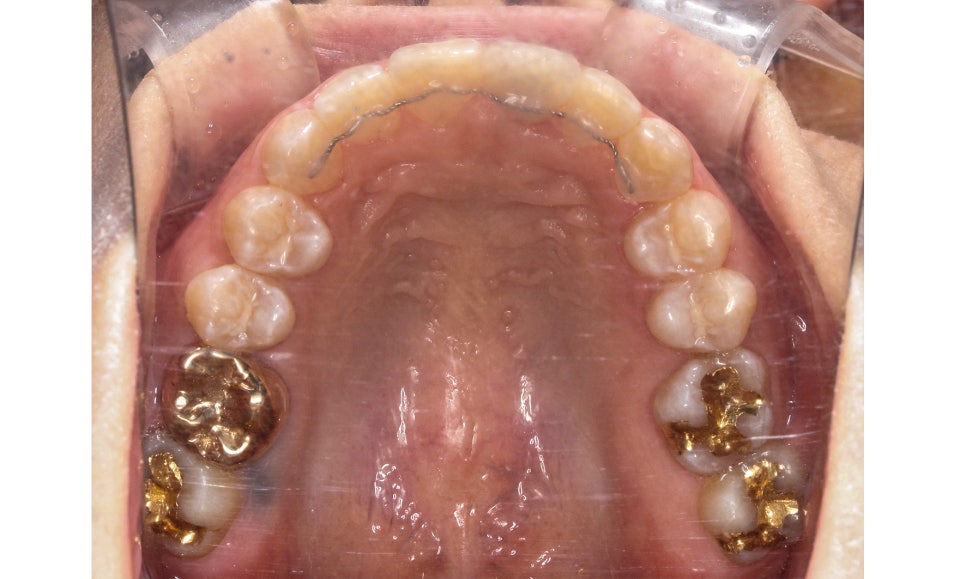

송곳니교정 전 상악의 교합면을 보면

사진에서 좌측 송곳니가 입술 방향으로

뻐드러지게 나가 있는 모습을 확인할 수 있습니다.

하악 교합면 역시 전치부의 치아들이

삐뚤거리며 자라있는 모습인데요,

위의 Case는 발치를 하지 않고

치아를 양악을 교정하는 것이기 때문에

부족한 악궁의 길이에 맞추어 치아가

배열될 수 있는 공간을 만들어 주는 것이 중요합니다.

양악교정 후 상악 교합면을 보시면

치아의 배열이 U자에 가까운 모습으로

바뀐 것을 확인할 수 있는데요,

가장 이상적인 안모라인이

형성되었기 때문에 구외사진에서도

안모가 변화된 것을 느끼실 수 있습니다.